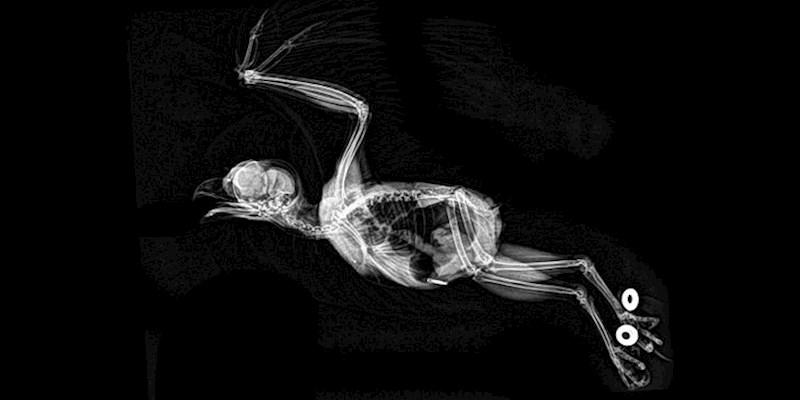

Sova